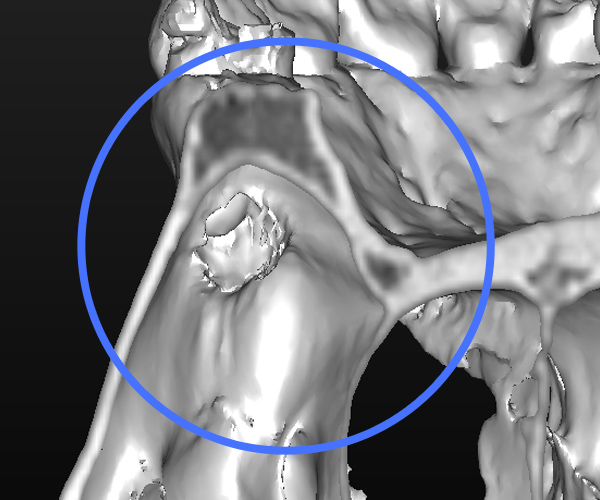

Before

左上3番の疼痛・腫れを主訴として来院

CT撮影により、歯性副鼻腔炎と診断